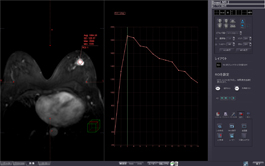

MR MULTIPARAMETRIC ANALYSIS

Using DCE MR images, this protocol displays high precision time-intensity curves for tissue characterization, with BI-RADS and general curve standardizations.